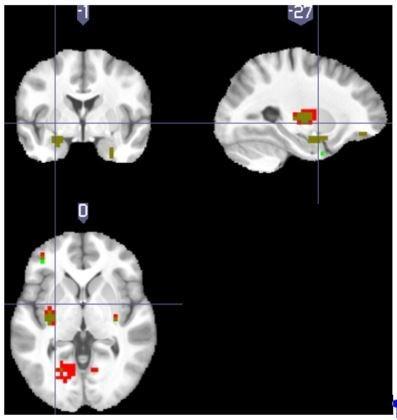

Tonic pain after injury characterises a behavioural state that prioritises recovery. Although generally suppressing cognition and attention, tonic pain needs to allow effective relief learning to reduce the cause of the pain. Here, we describe a central learning circuit that supports learning of relief and concurrently suppresses the level of ongoing pain. We used computational modelling of behavioural, physiological and neuroimaging data in two experiments in which subjects learned to terminate tonic pain in static and dynamic escape-learning paradigms. In both studies, we show that active relief-seeking involves a reinforcement learning process manifest by error signals observed in the dorsal putamen. Critically, this system uses an uncertainty ('associability') signal detected in pregenual anterior cingulate cortex that both controls the relief learning rate, and endogenously and parametrically modulates the level of tonic pain. The results define a self-organising learning circuit that reduces ongoing pain when learning about potential relief.